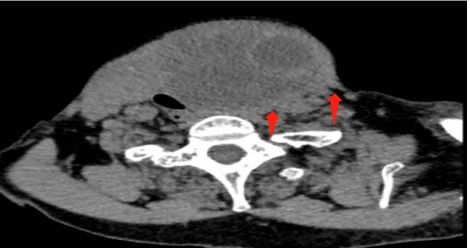

78岁的刘奶奶因颈部巨大甲状腺肿困扰多年,家人带她求医问药,但因种种原因没有继续治疗,今年以来她自感肿块越来越大,严重影响到生活起居,于是家人便带她至我院甲状腺科诊治,在术前的颈部CT显示,肿块已经导致气管、食管明显受压、移位。当务之急是要尽早手术切除,解除压迫。

因为术前做好了充足的准备,巨大的甲状腺肿物被完整切除,其周围的重要神经、血管、气管和食道均未损伤。孙磊介绍,这是甲状腺病区迄今为止切除的最大甲状腺肿物,请有甲状腺肿物的患者要注意密切随访,防止肿物的增大造成气管、食管等重要脏器的受损,同时肿物的增大也会增加手术的难度,术后更容易产生各种并发症。